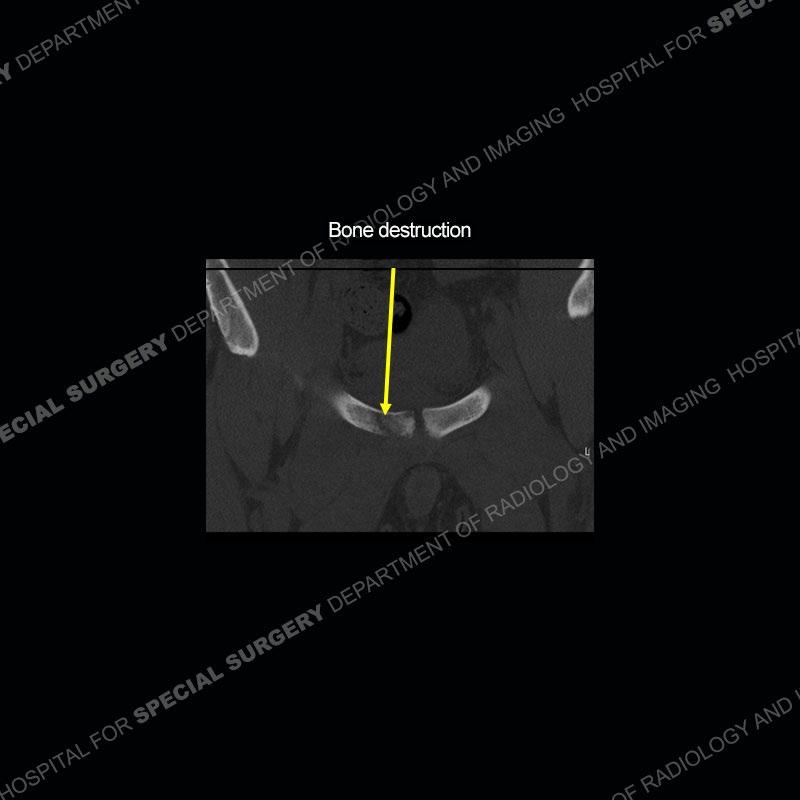

Radiographs did not demonstrate any clear abnormality. The MRI shows markedly abnormal signal of the right superior pubic ramus and abnormal signal/”mass” extending into the adjacent soft tissue. The inferior articular surface of the ramus showed what was thought to be bony destruction. CT examination shows a destructive process of the right superior pubic ramus.

This case was a bit surprising to all involved given that the young man is otherwise in good health and extremely active in sports. The original thought was this case was going to be an overuse injury or stress fracture. The pubic ramus with the adjacent physis acts as a metaphyseal equivalent and although not frequently thought of would be a reasonable location for infection/osteomyelitis. The first MRI was somewhat confusing as the process did not have an appearance of a stress injury or rectus adductor aponeurosis injury. The degree of edema of the bone and soft tissue together would be odd especially for a sports hernia process. Initially, the thought was of an aggressive process which could be infection or neoplastic. Particularly, the abnormal architecture of the inferior surface of the ramus looked like a destructive process.

The repeat MRI, with the marked degree of increased abnormality of the bone and soft tissue shifted the diagnosis to a high degree towards infection. Even the most aggressive of neoplasms would not have that the degree of change in a 3-day time span. The CT study was shown before the repeat MRI but actually occurred just after the repeat MRI. It helped confirm the destructive process of the ramus and particularly the abnormal architecture along the inferior margin. The patient went on to have a CT guided aspiration of one of the soft tissue collections with 4cc of purulent fluid obtained. A surgical irrigation and debridement of the bone and soft tissue was performed. A PICC line was placed and the patient is currently undergoing IV antibiotic treatment with a possible repeat irrigation and debridement.